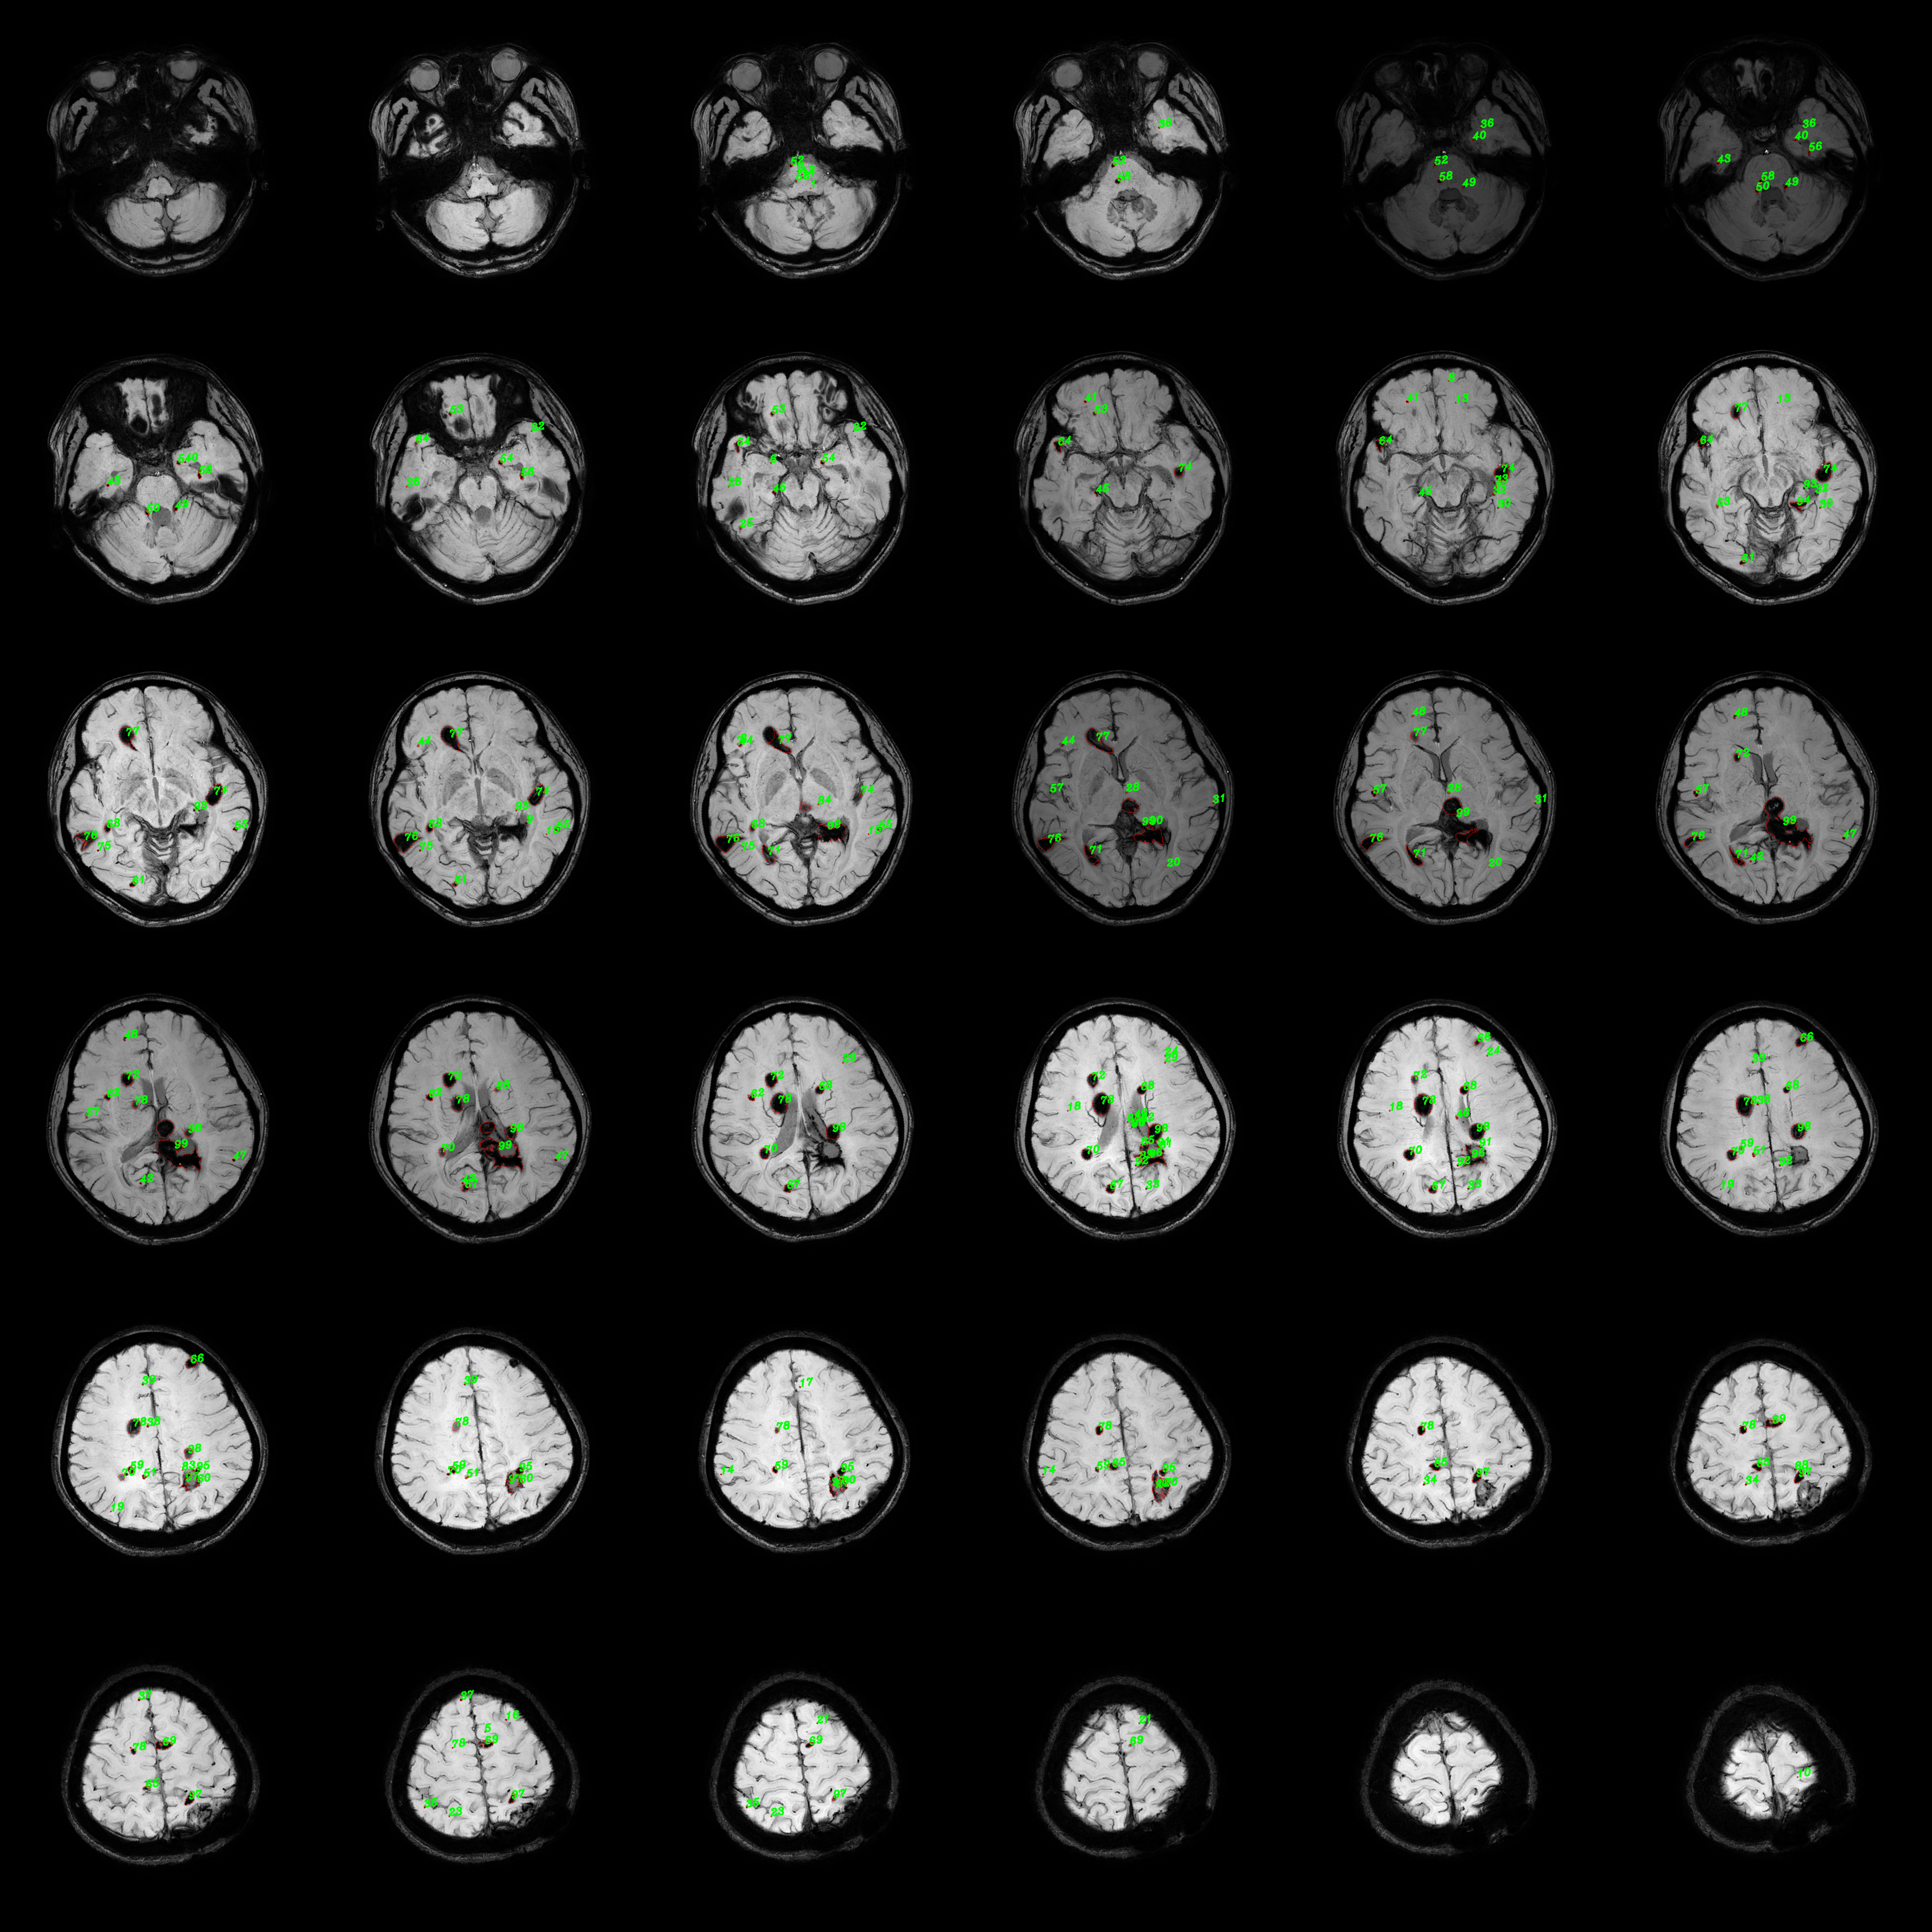

However, presently, statistical analysis of lesion volume and quantity in FCCM relies predominantly on manual measurement methods. Due to the complexity and large number of lesions, especially the presence of numerous small lesions as illustrated in Figure 1, manual measurement of their volume and quantity is almost impossible. Consequently, current manual measurements primarily focus on larger lesions, yet are unavoidably subject to the influence of physicians’ subjective cognition, resulting in certain measurement inaccuracies. Moreover, due to the large number of lesions, clinicians find it challenging to detect progressive lesions with the naked eye. Therefore, there is an urgent demand for an objective and precise method to quantitatively assess lesion volume and quantity in FCCM patients. Simultaneously, it is anticipated that a reference for identifying clearly progressing lesions between two MRI images can be provided to clinicians by this method.

Refer to caption

Figure 1: Complex FCCM lesion cases. The green markings represent the regions of lesions.

5.2 Efficiency of annotation strategy

To validate the efficiency of the proposed annotation method, we select 50 FCCM images for annotation by clinicians, involving both contour tracing and bounding box annotation. Considering the feasibility of contour tracing annotation, images with moderate number and size of lesions are chosen. The time required for lesion contour annotation across the 50 images is approximately 96 minutes, while bounding box annotation takes only 25 minutes. Moreover, the screening of segmentation annotation results for SAM and BBTS takes less than 5 minutes. In summary, the annotation method we proposed can save doctors over 60% of annotation time. Moreover, this has not taken into account the annotation of images with numerous and small lesions as shown in Figure 1. Subsequently, through iterative training annotation with segmentation networks, the workload for clinicians is further reduced, thereby enhancing annotation efficiency.